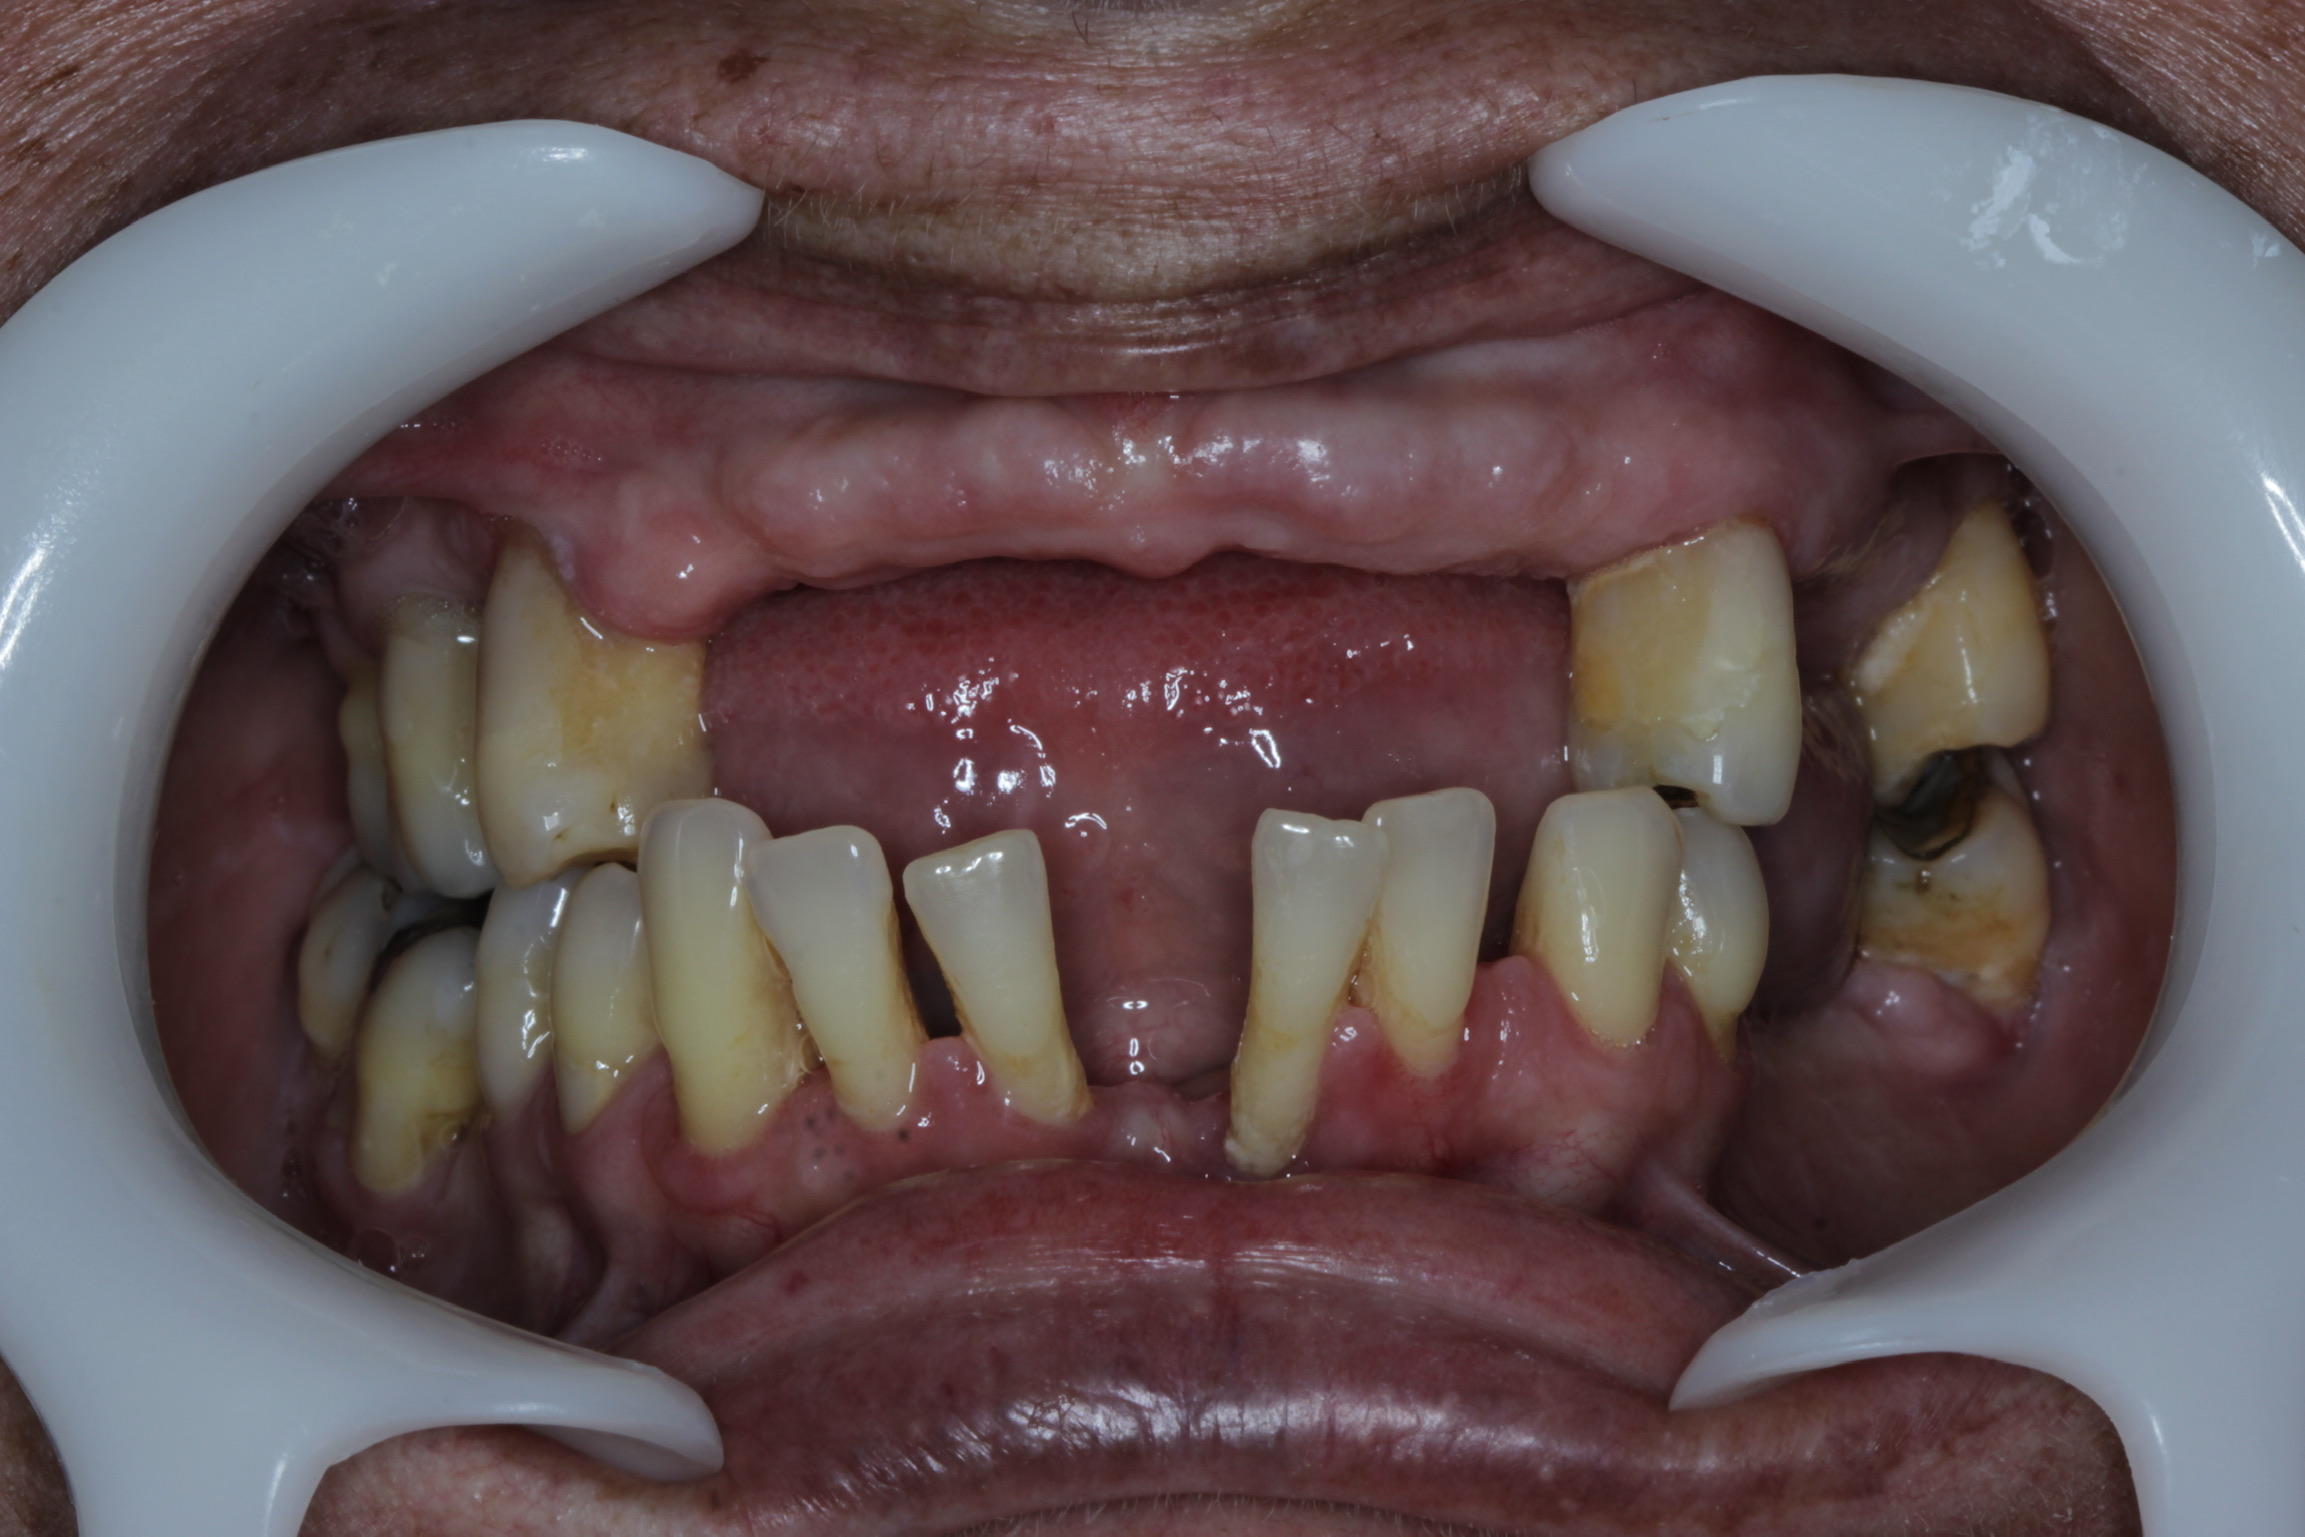

Sabemos que a ansiedade e o estresse podem fazer mal para a saúde do corpo, mas você sabia que também pode afetar a qualidade do seu sorriso e ainda contribuir para a queda dos dentes?

Segundo um estudo realizado por pesquisadores da Universidade Estadual de Campinas (Unicamp), ter uma rotina estressante pode resultar em prejuízos para a saúde bucal. Quem é mais estressado ou sofre de ansiedade crônica tem maiores chances de desenvolver doenças bucais que podem resultar até na perda dos dentes.

Isso ocorre porque o cansaço extremo, falta de sono, nervosismo e ansiedade contribuem para a diminuição do fluxo salivar ou provocam o ranger dos dentes durante o dia e à noite, o que pode causar fraturas graves nos dentes.

• O bruxismo é uma doença caracterizada pelo ranger ou forte pressão nos dentes. De acordo com a Organização Mundial da Saúde (OMS) essa doença atinge cerca de 84 milhões de brasileiros;

• A periodontite consiste em uma inflamação ou infecção crônica que atinge os tecidos que estão ao redor do dente e que o sustenta.

Essas doenças são tratáveis e podem até ser curadas através do diagnóstico precoce. Com a avaliação de um dentista é possível descobrir o estágio da doença e quais serão os procedimentos necessários, variando de paciente para paciente. Em caso de perda dos dentes, a reabilitação por meio do uso de implantes é o mais recomendável.